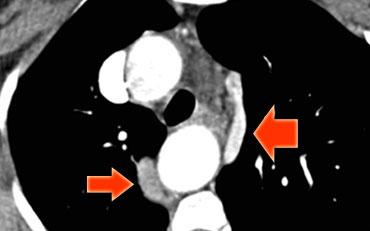

Describe the images on the left and then continue reading.

On the left side there is a vascular structure, that runs inferiorly below the level of the left hilum and enters into a dilated coronary sinus.

The diagnosis is left or double superior vena cava.

Left Superior Intercostal Vein.

This is an anastomosis between the accessory hemiazygos vein and the left brachiocephalic vein.

It courses along the lateral margin of the aortic arch (‘aortic nipple’).

It is a normal variant and if you look for this structure you will frequently notice it.